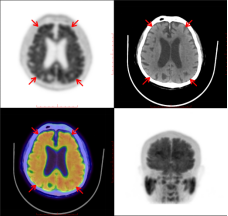

张大爷Aβ脑PET显像呈典型AD表现:皮质灰质放射性示踪剂摄取,从白质延伸至皮质带,致使灰白质分界模糊